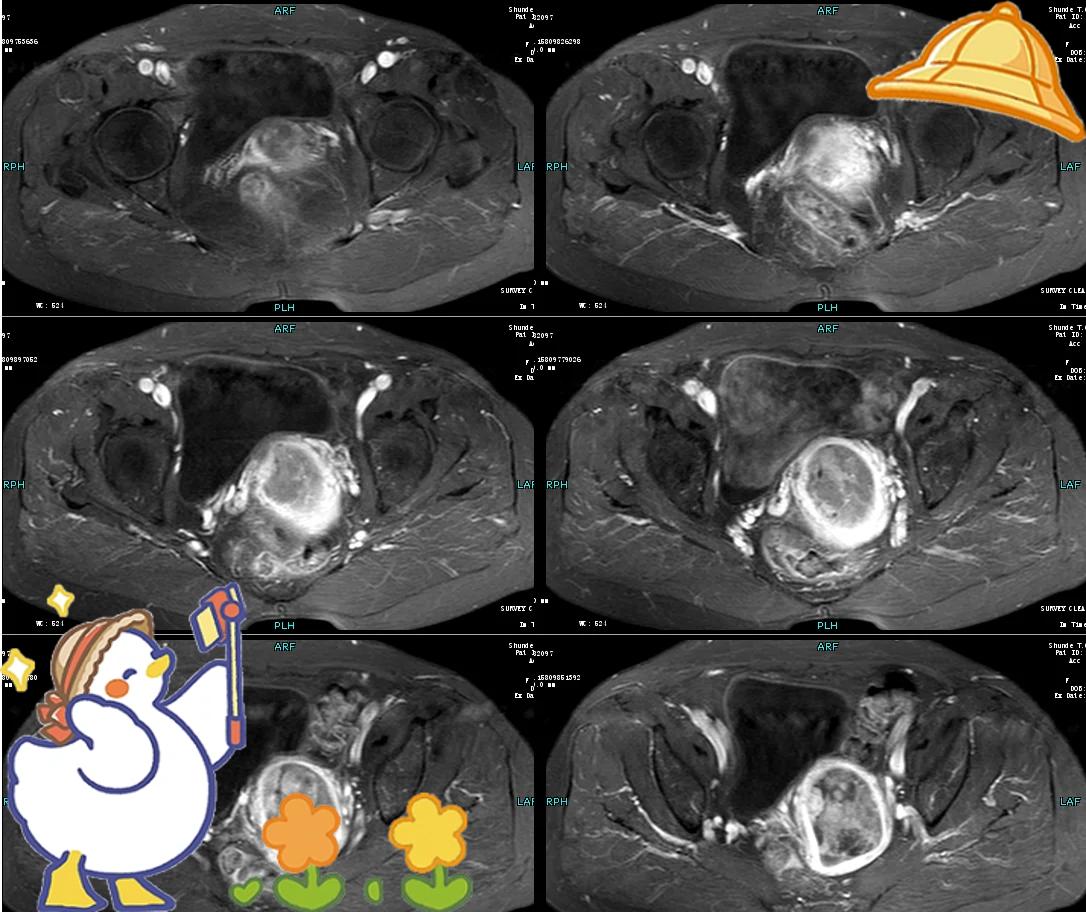

子宫内膜癌早期出血的症状主要包括以下方面绝经后阴道流血是子宫内膜癌的典型早期表现,尤其需引起重视绝经后女性若出现阴道出血,即使量少呈暗红色或间歇性稀薄血水,也应警惕此症状与正常绝经后生理状态明显不同,是子宫内膜癌的重要预警信号月经紊乱常见于未绝经女性,表现为月经周期或经量的异常患者可能出现月经过多经。

子宫内膜癌早期的出血特点主要表现为持续或间断性的不规则阴道流血以下是具体的特点出血量和颜色出血常为少量至中等量少量出血时,血液可能呈现粉色或暗褐色大量出血时,则多为鲜红色出血模式出血可能是持续性的,也可能是间断性的,没有固定的出血规律与月经的关系生育年龄女性可能表。